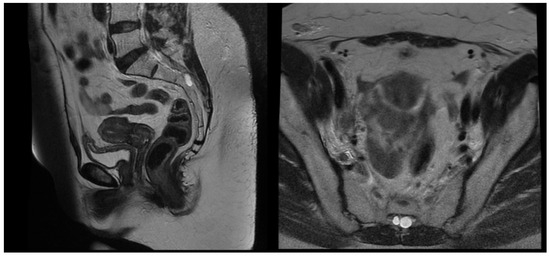

After pre-treatment quality assurance, the patient began the external beam IGRT and concurrent chemotherapy with Cisplatin 40 mg/kg weekly. The first Cisplatin infusion was given with the first fraction, and the patient received a total number of five cycles. External beam radiotherapy (EBRT) was performed on a linear accelerator Elekta Synergy Platform with daily cone beam CT imaging ensuring the proper patient set-up and reproducible bladder and rectum filling. The EBRT was delivered in 38 days. The treatment was well tolerated by the patient, and no early toxicity was detected during the chemoradiation course. She was scheduled for an MRT scan two days before the last EBRT fraction to assess the tumor response, depth of uterine cavity, and preferred angle of the tandem for cervical brachytherapy. The MRT scan revealed that the gross tumor had shrunk to 15 mm in its maximal diameter, and all previously enlarged lymph nodes were undetectable except for the right external iliac lymph node, the size of which decreased from 29 mm to 15 mm with a necrotic center (Figure 4). After gynecological examination and signing an informed consent, the patient was scheduled for intracavitary electronic brachytherapy (EBT).

Figure 4.

T2 weighted MRT images after EBRT.